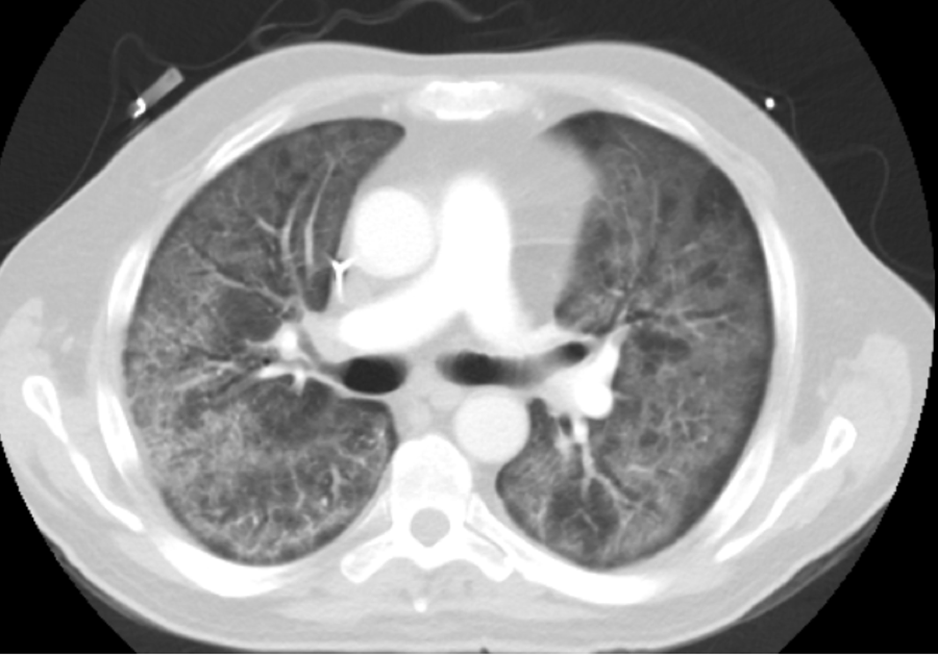

A 65-year-old male with a past medical history significant for T-cell lymphoma presented to Ascension Providence Hospital due to worsening dyspnea, diffuse weakness, and fever. Of importance, two months prior to admission to the hospital, he was diagnosed with stage IVA CD30 positive peripheral T-cell lymphoma not otherwise specified with cutaneous and pulmonary involvement (Figure 1). He was started on therapy with brentuximab, doxorubicin, cyclophosphamide, and prednisone with planned future evaluation for stem cell transplantation. He received two cycles of therapy and at a follow-up visit to the clinic, he was directed to the emergency department due to worsening respiratory symptoms.

Figure 1. CT chest showing soft tissue attenuation right hilar mass encasing the right main pulmonary artery and bronchi without significant associated narrowing. The overall size measures approximately 4.7 x 4.1 x 2.7 cm with prominent left hilar lymph nodes concerning lymphoma.